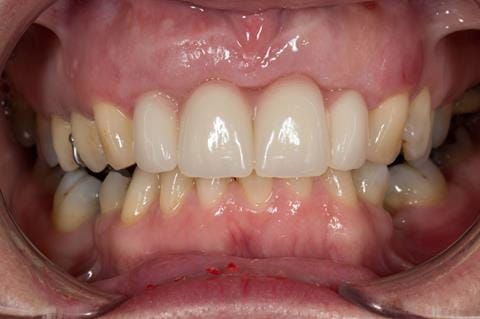

- Extract the upper 2-2 teeth and replace with an interim acrylic based partial denture. Reline the interim denture over 9 - 12 months, replacing with a definitive cobalt chromium based partial denture. The definitive denture would ideally be designed as an occlusal protective splint to reduce the the potential for mechanical wear and breakages of the moderately/heavily restored maxillary dentition. In addition, should further upper teeth require extraction they could be added on to the denture cobalt chromium framework - therefore a new prosthesis would not be required as future teeth are lost. This option would produce an excellent aesthetic outcome. This is the option the patient chose to have.

Following consultation and second discussion appointment the patient chose to have option 3 namely, a maxillary cobalt chromium based partial denture/protective occlusal splint. The clinical situation and treatment process is shown in detail below with photographs. The patient was successfully rehabilitated with this and her quality of life considerably improved. The clinical work was provided by Finlay and the technical work by Rowan.